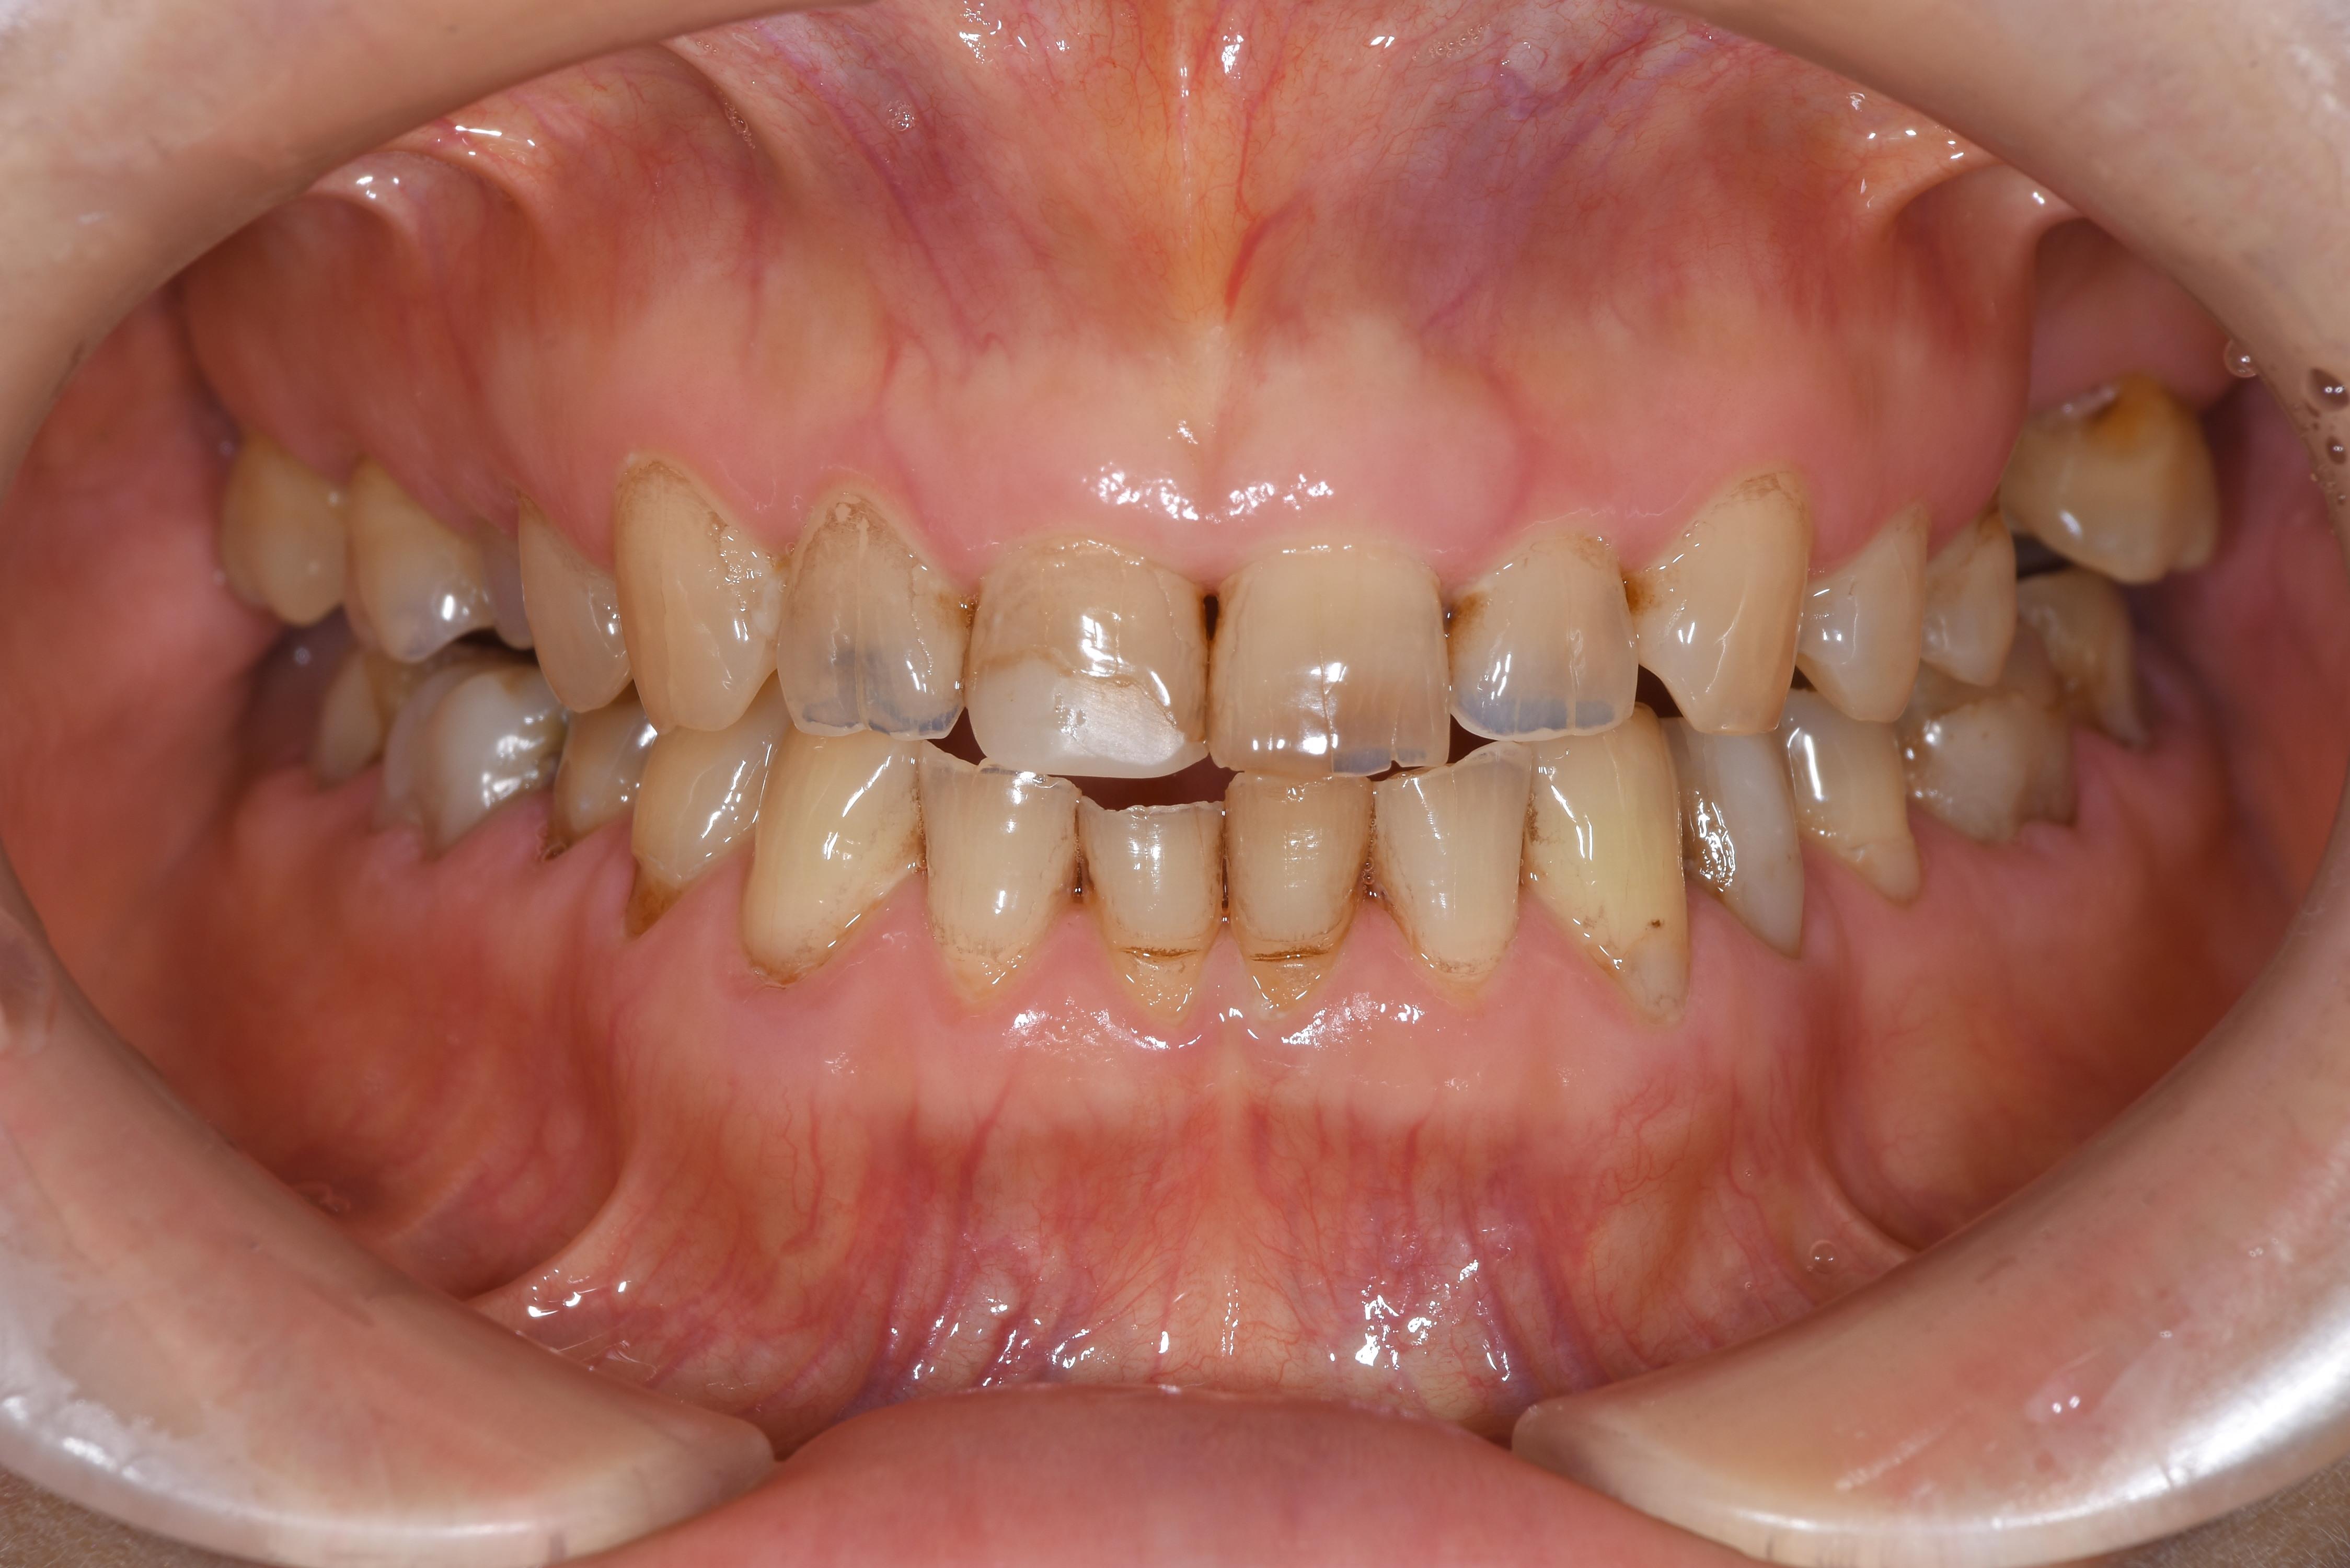

治療前

| 治療内容 | セラミック | 期間 | 約6か月 |

|---|---|---|---|

| 治療回数 | 20回 | 費用 | 約300万(処置費用、仮歯、プロビジョナルを含む) |

| リスク 副作用 |

全て神経を保存して治療しておりますので、セット後に刺激により神経を除去する可能性がリスクとして存在します | ||